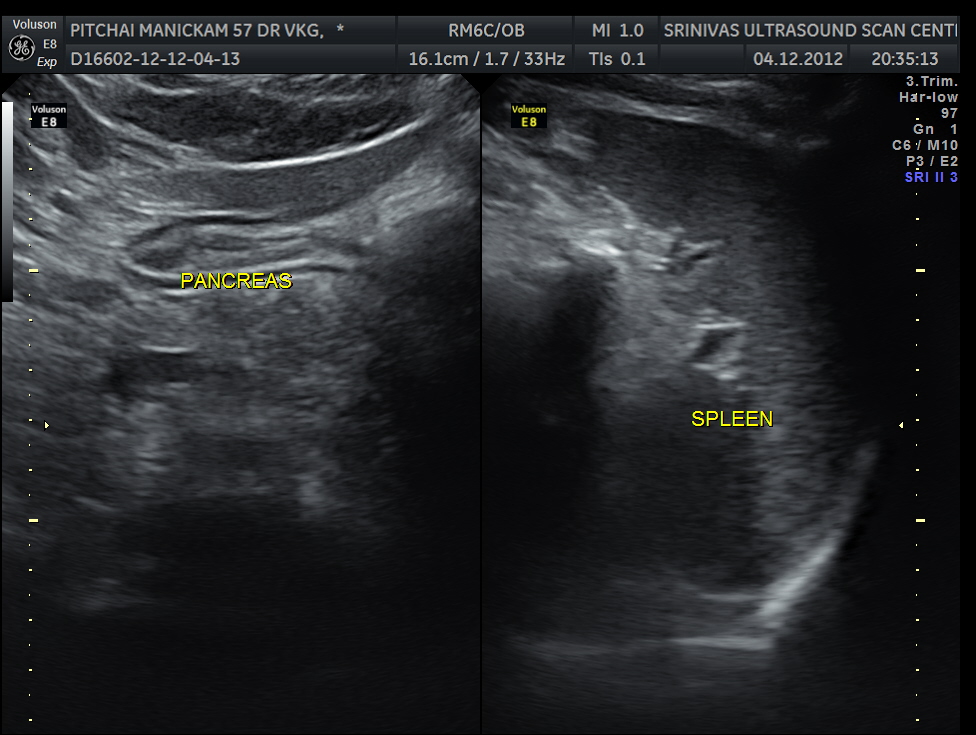

Liver, gall bladder , pancreas, spleen and the left kidney were normal . The prostate showed mild enlargement.